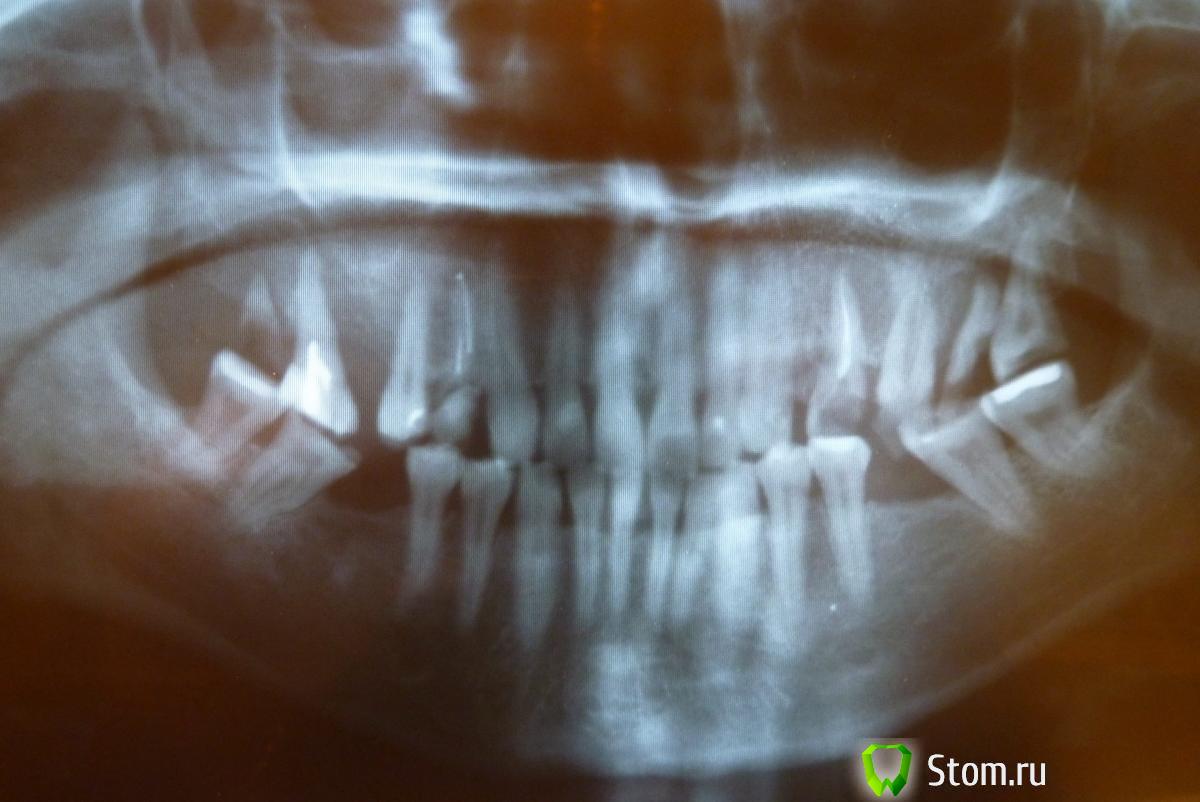

Фрида-77 Опубликовано 18 февраля, 2012 Поделиться Опубликовано 18 февраля, 2012 Хочу заняться зубками, т.к. выпали пломбы.Зубы не болят и не беспокоят. Подскажите,что с ними делать? Реставрация или протезирование? Имплантация отпадает (есть противопоказания).Спасибо,жду ответов. Трудно неспециалисту разобраться ))) Ссылка на комментарий

Фрида-77 Опубликовано 18 февраля, 2012 Автор Поделиться Опубликовано 18 февраля, 2012 Смотрела,вглядывалась...кажется всё наоборот-снимок в зеркальном отражении))) Ссылка на комментарий

DmitrySH Опубликовано 18 февраля, 2012 Поделиться Опубликовано 18 февраля, 2012 У Вас сильная патологическая стираемость зубов. Тут без осмотра в кресле трудно советовать. Ссылка на комментарий

DmitrySH Опубликовано 24 февраля, 2012 Поделиться Опубликовано 24 февраля, 2012 Нет, фото не вариант. Потребуется комплексное лечение: терапия, хирургия, ортопедия, может еще и ортодонтия Ссылка на комментарий